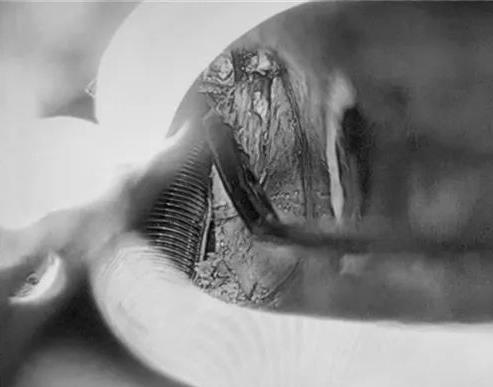

低温等离子早期喉癌切除术

早在2006年,红河州第三人民耳鼻咽喉-头颈外科在红河州率先引入低温等离子技术,在临床应用了16年,目前已广泛应用于儿童扁桃体及腺样体切除、鼾症的治疗,尤其在鼻咽部肿瘤、咽喉肿瘤以及早期喉癌治疗中的应用,通过选择合适的患者,进行低温等离子微创手术治疗,使手术更精准,恢复更快,减少局部损伤,促进早期康复,取得良好的临床治疗效果。

邓泽海副主任医师以《鼻内镜等离子下复发性鼻咽癌切除术、颅底粘膜瓣修复术》为题目,围绕肿瘤切除及颅底修复为主题,通过分享手术视频,详细向大家展示了局灶复发性鼻咽癌的手术切除过程要点及外科肿瘤手术切除理念(切缘阴性保证彻底切除病灶及修复重建)。